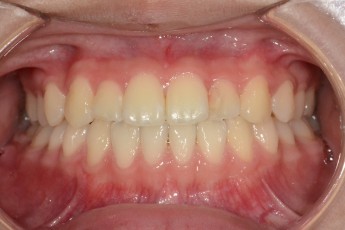

BEFORE & AFTER

- 과개교합교정